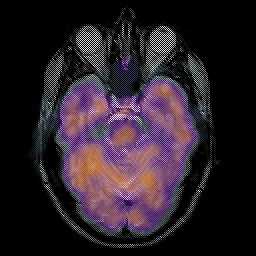

Glioma overlay -- Slice #9

[Home][Help][Clinical] Slice 9